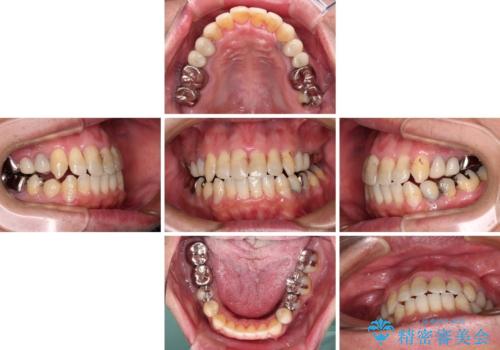

- 飛び出している上顎前歯と、奥歯に多くある銀歯を気にして来院された患者様です。

マウスピースで矯正を行いたい反面、一旦早めに前歯を整えたいというご希望があったため、まずは上顎前歯をワイヤー装置で整え、その後インビザラインにて仕上げていくこととしました。

矯正治療後には、奥歯の銀歯をすべてセラミックにて補綴治療することとしました。

ワイヤー矯正を併用したことで、上顎前歯はあっという間に整いました。

補綴治療にあたり、痛みのある歯に対して根管治療を行うこととしましたが、処置が必要な歯が多かったため、期間を要しました。

補綴治療中に前歯のデコボコが戻ってしまったため、補綴治療後にインビザラインを1セット追加して仕上げました。